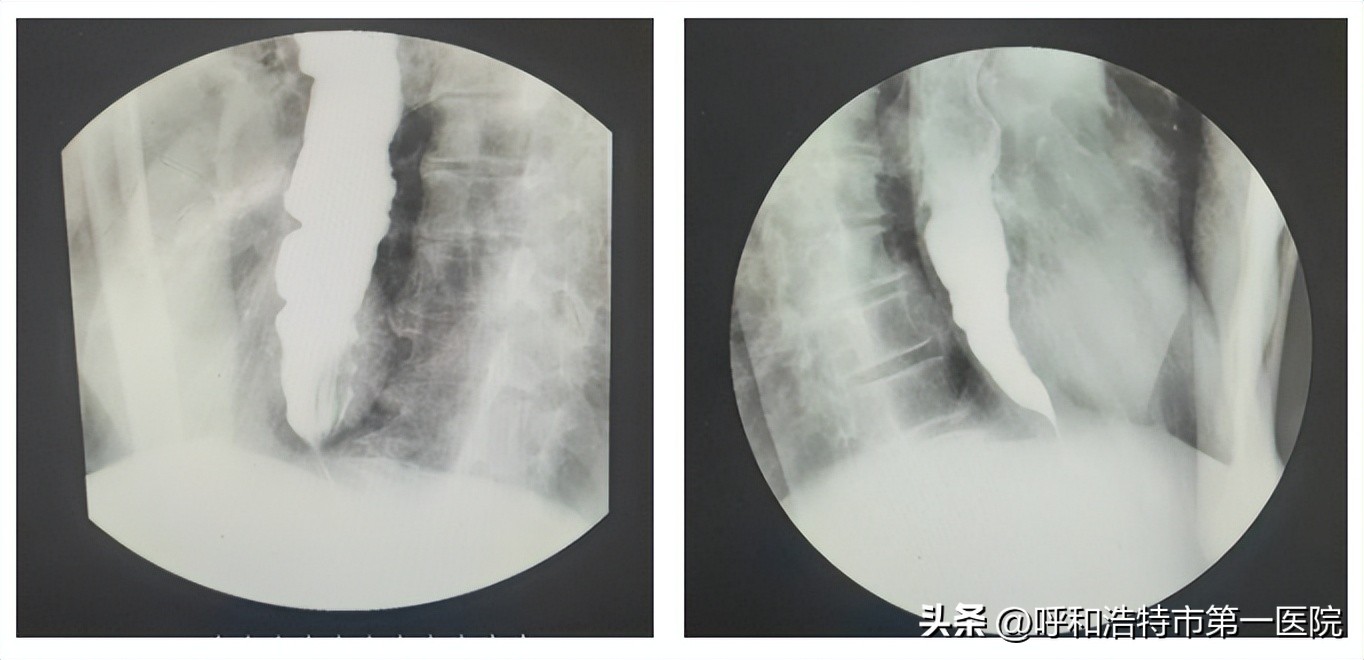

上消化道造影提示:食管中下段扩展,贲门呈“鸟嘴样”改变。

胃镜提示:食管中下段扩展,其内有潴留液和食物残渣,贲门狭窄明显,内镜通过困难,更换超细胃镜后通过,胃黏膜可见散在糜烂,流出道通畅。内镜下给予患者留置胃管于胃腔内。